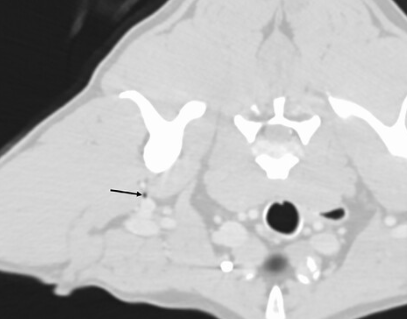

CT 촬영을 하다 보면 실제 공기방울이 심심치 않게 발견된다. 모두 의학적 이유로 발생한 것일까? 에 대한 궁금증을 풀어줄 논문이 나와 소개한다.

근육조직에서도 발견되기도 하고 심지어

척수강 내에서도 발견되기도 한다.